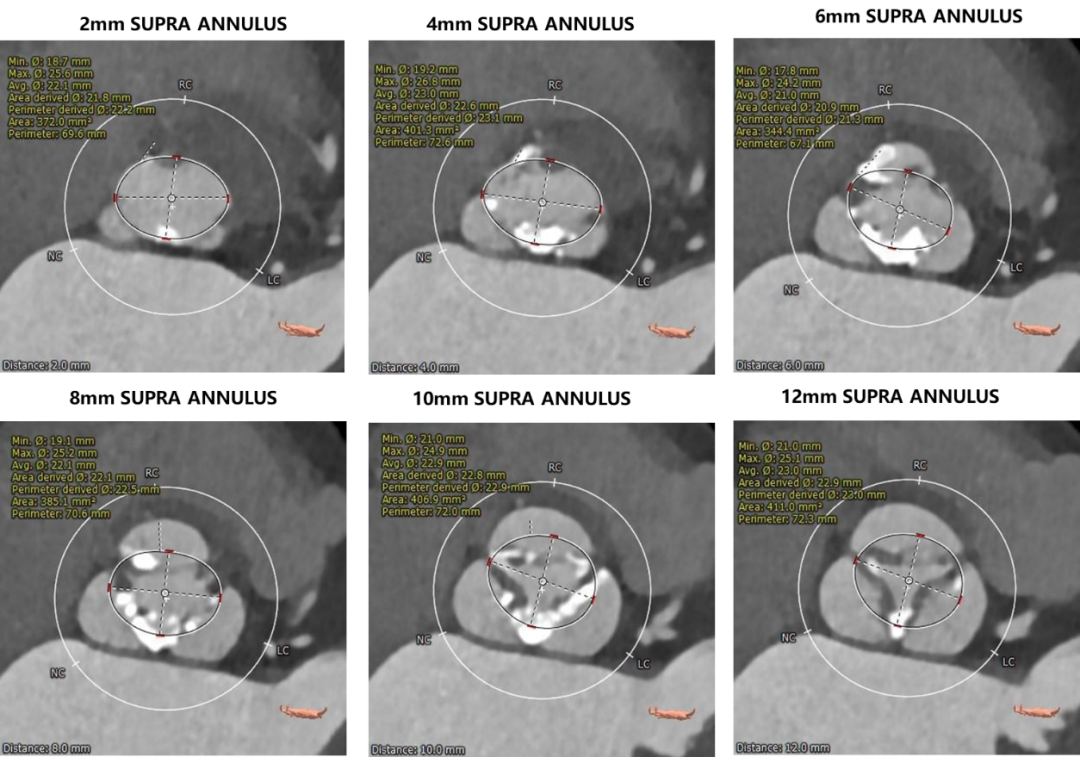

瓣环上测量